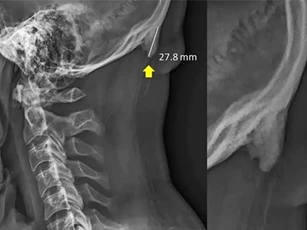

Nghe có vẻ khó tin, nhưng theo một nghiên cứu từ các nhà khoa học Úc, việc liên tục sử dụng smartphone có thể khiến chúng ta mọc một chiếc “sừng” ngay trên hộp sọ.

DNVN - Các nhà khoa học Australia vừa công bố một nghiên cứu gây sốc cho giới trẻ. Theo đó, việc liên tục sử dụng smartphone trong thời gian dài có thể khiến con người mục một chiếc sừng ngay trên hộp sọ.